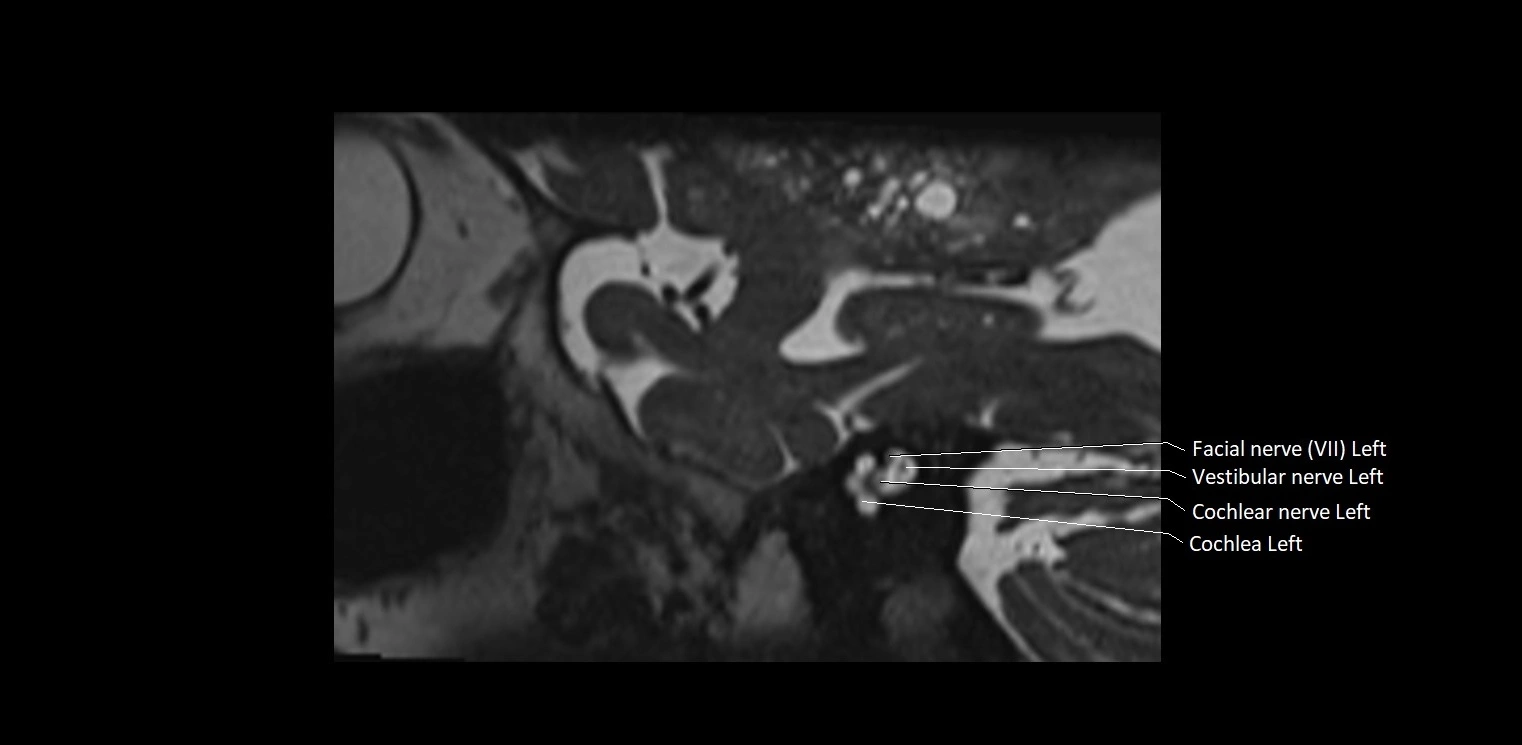

MRI Appearance

• The abducens nerve is a small, thin, linear structure

• Best visualized on high-resolution T2-weighted 3D MRI sequences (e.g., FIESTA or CISS)

• Seen as a hypointense (dark) line running from the brainstem at the pontomedullary junction, traversing the prepontine cistern, and entering Dorello’s canal under the petrosphenoidal ligament, then into the cavernous sinus, and finally the orbit

• May be challenging to visualize in standard MRI due to its small size

• Pathology may be inferred by absence, displacement, or enhancement of the nerve